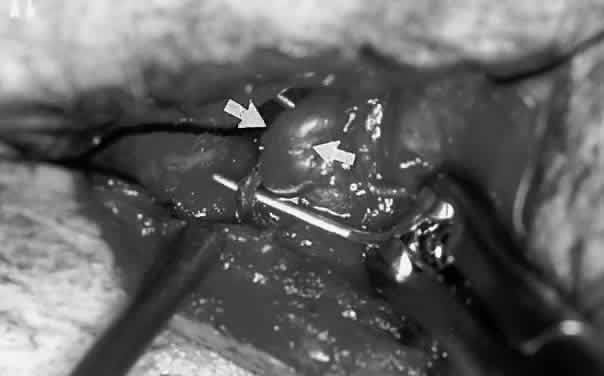

In patients with unsuccessful transarterial embolization of cavernous-dural fistulas, a medial lid crease or a sub-brow incision can be used to locate the dilated anterior superior ophthalmic vein for transvenous embolization (Fig. 23; see also Volume 2, Chapter 17, Fig. 21C). Sharp dissection is carried superiorly in the preseptal plane until the arcus marginalis is reached. The orbital septum is incised along the width of the skin incision. The trochlea and superior oblique tendon are identified and insulated with neurosurgical cottonoids. The orbital fat adjacent to the trochlea is moved laterally with a pair of malleable retractors. Orbital fat septa are bluntly dissected apart to prolapse the superior ophthalmic vein forward. Once identified, the vessel is insulated with ½-inch neurosurgical cottonoids to prevent herniating fat from obscuring the surgical field. Two 2-0 silk ligatures are placed around the vein for traction. A guidewire is introduced through a venipuncture between the two ligatures. An angiographic catheter is threaded over the guidewire and secured to the vessel with a silk suture. With successful closure of the shunt, the vessel is no longer arterialized. The silk ligatures are then loosened and the venipuncture site cauterized with a bipolar cautery.

Fig. 23. Exposure of supraorbital vein (arrows) for endovascular interventional closure of cavernous sinus fistula.